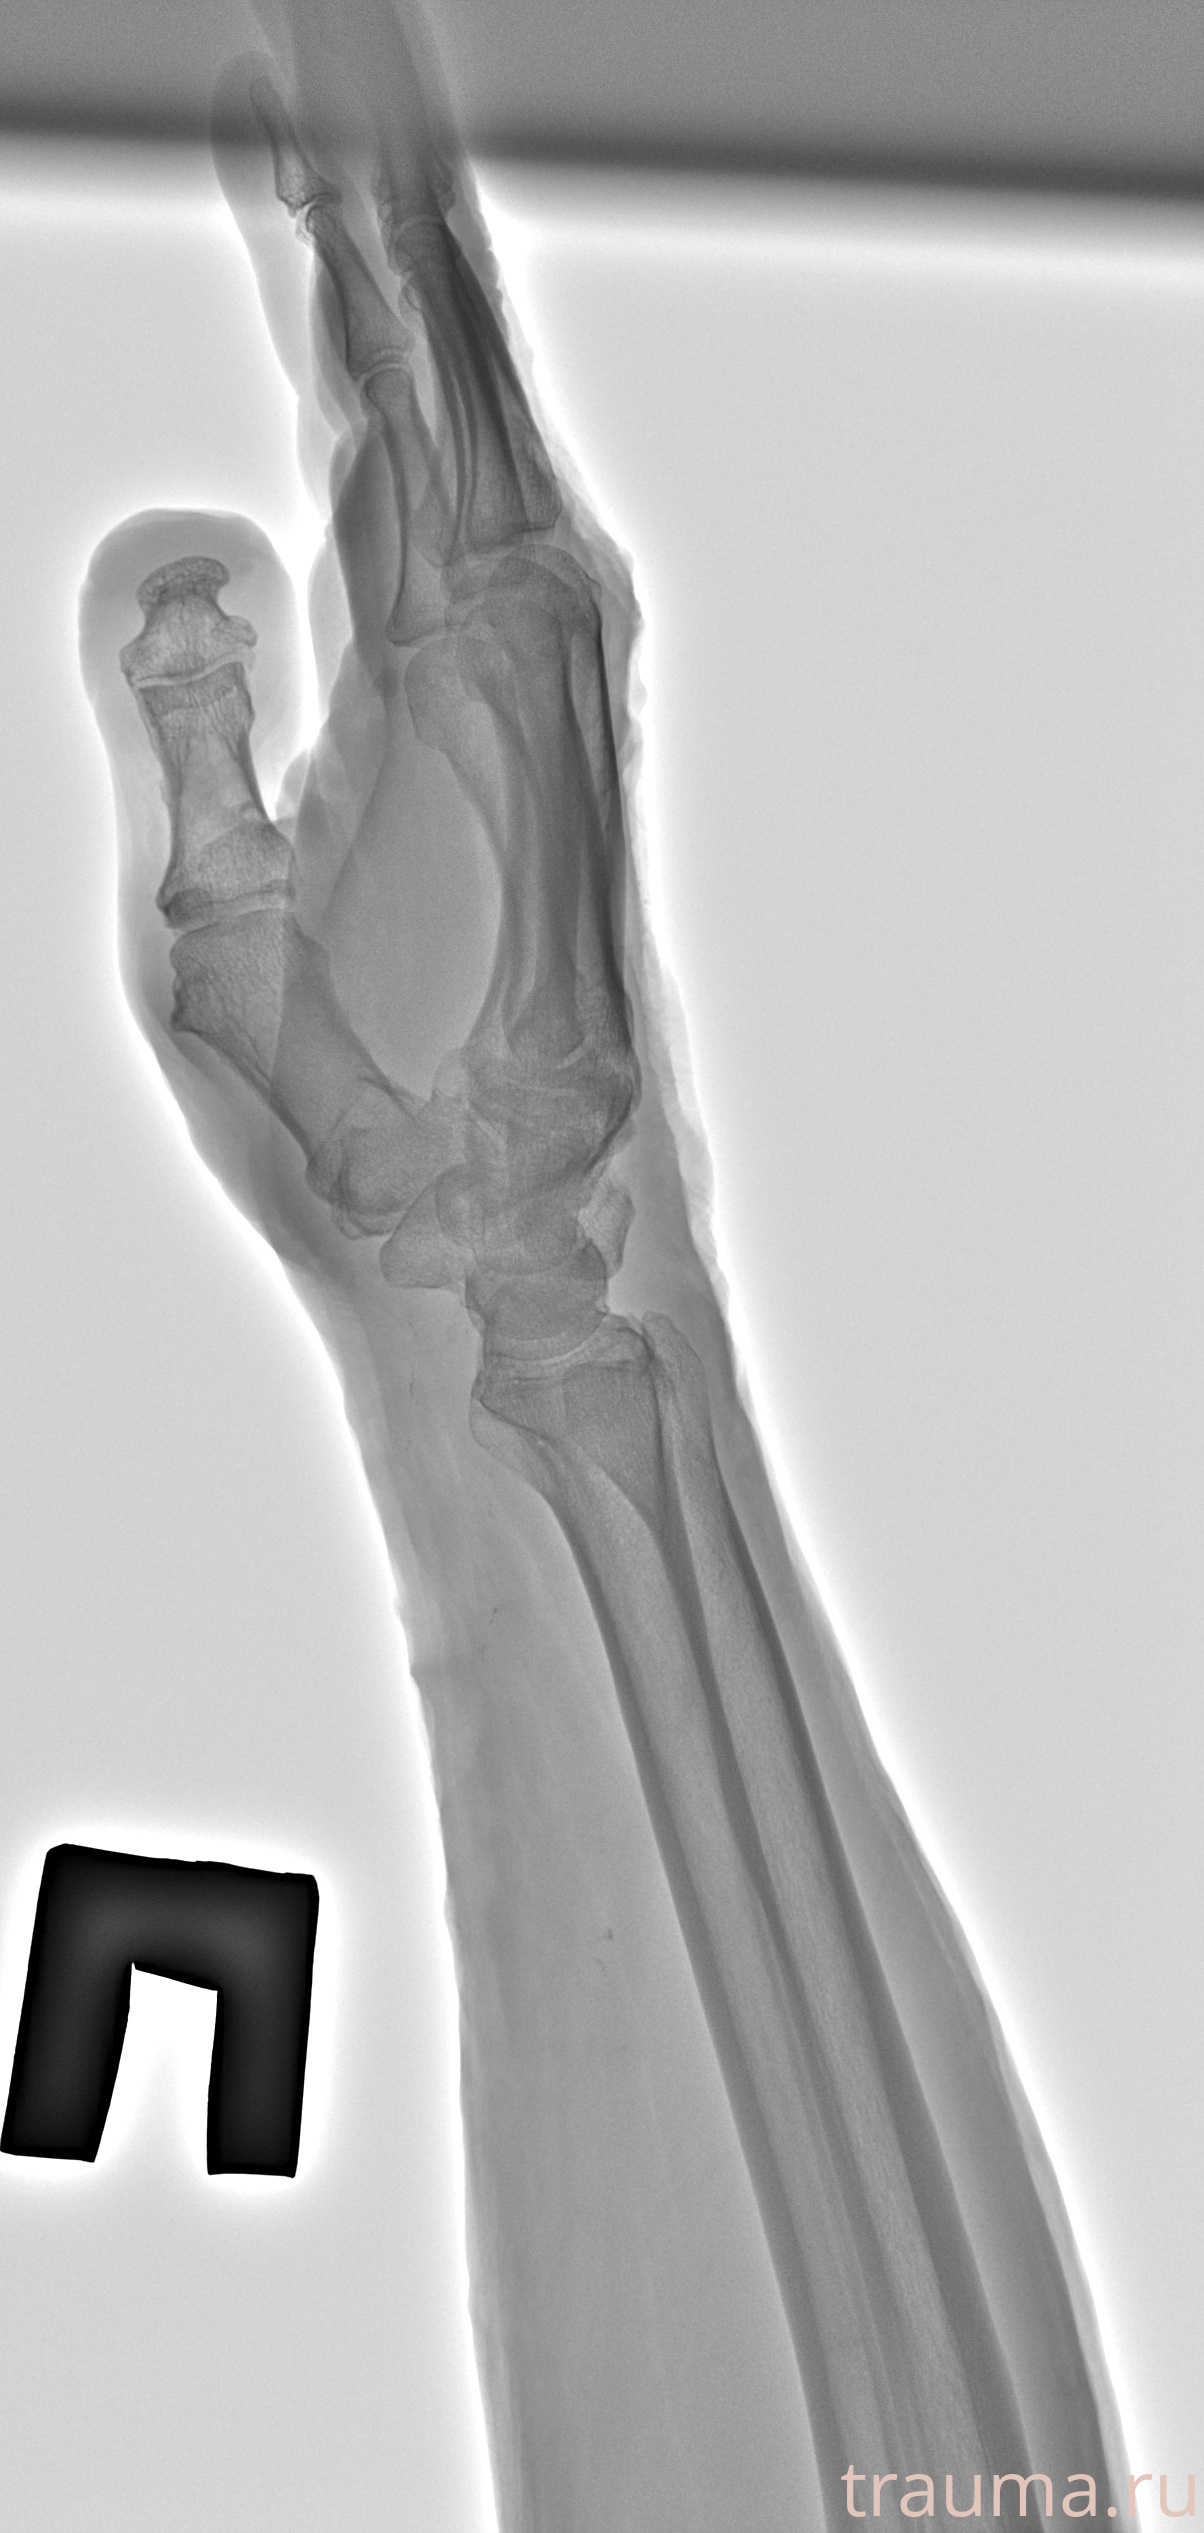

Рентгенограммы

Рентген на дому: по вашему адресу приезжает врач-рентгенолог, травматолог-ортопед с мобильным рентгеновским аппаратом, проводит диагностику травмы или заболевания, делает необходимые рентгенограммы, дает рекомендации по дальнейшему лечению. Получить качественные снимки в домашних условиях возможно благодаря уникальной методике, разработанной МосРентген Центром для института  Склифосовского